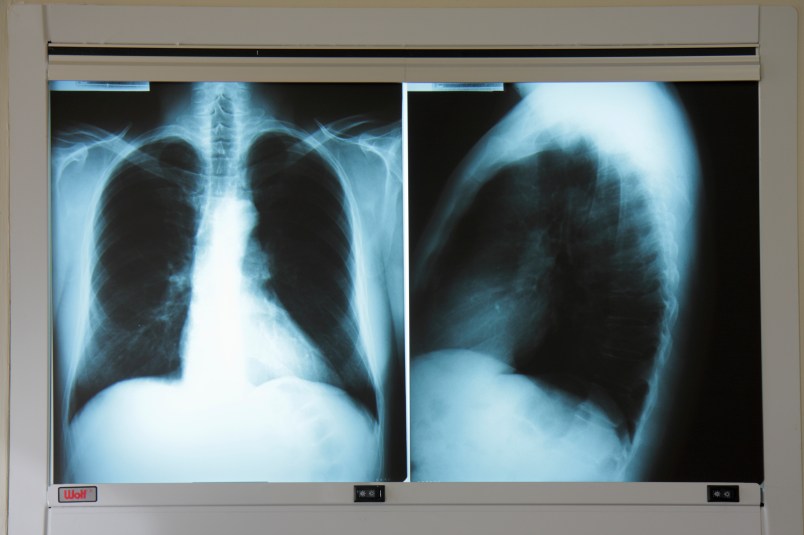

Radiation is everywhere, from potassium in bananas to the microwaves popping our popcorn. Most of it is benign. But what’s of concern is the higher-energy, shorter-wave radiation, like X-rays, that can penetrate and disrupt living cells, sometimes causing cancer.

“Even exposures below 100 millisieverts” — an amount roughly equivalent to 25 chest X-rays or about 14 CT chest scans — “slightly increase the risk of getting cancer in the future,” the agency’s guidance said.

BTW, that x-ray on the right looks like a shark attack.